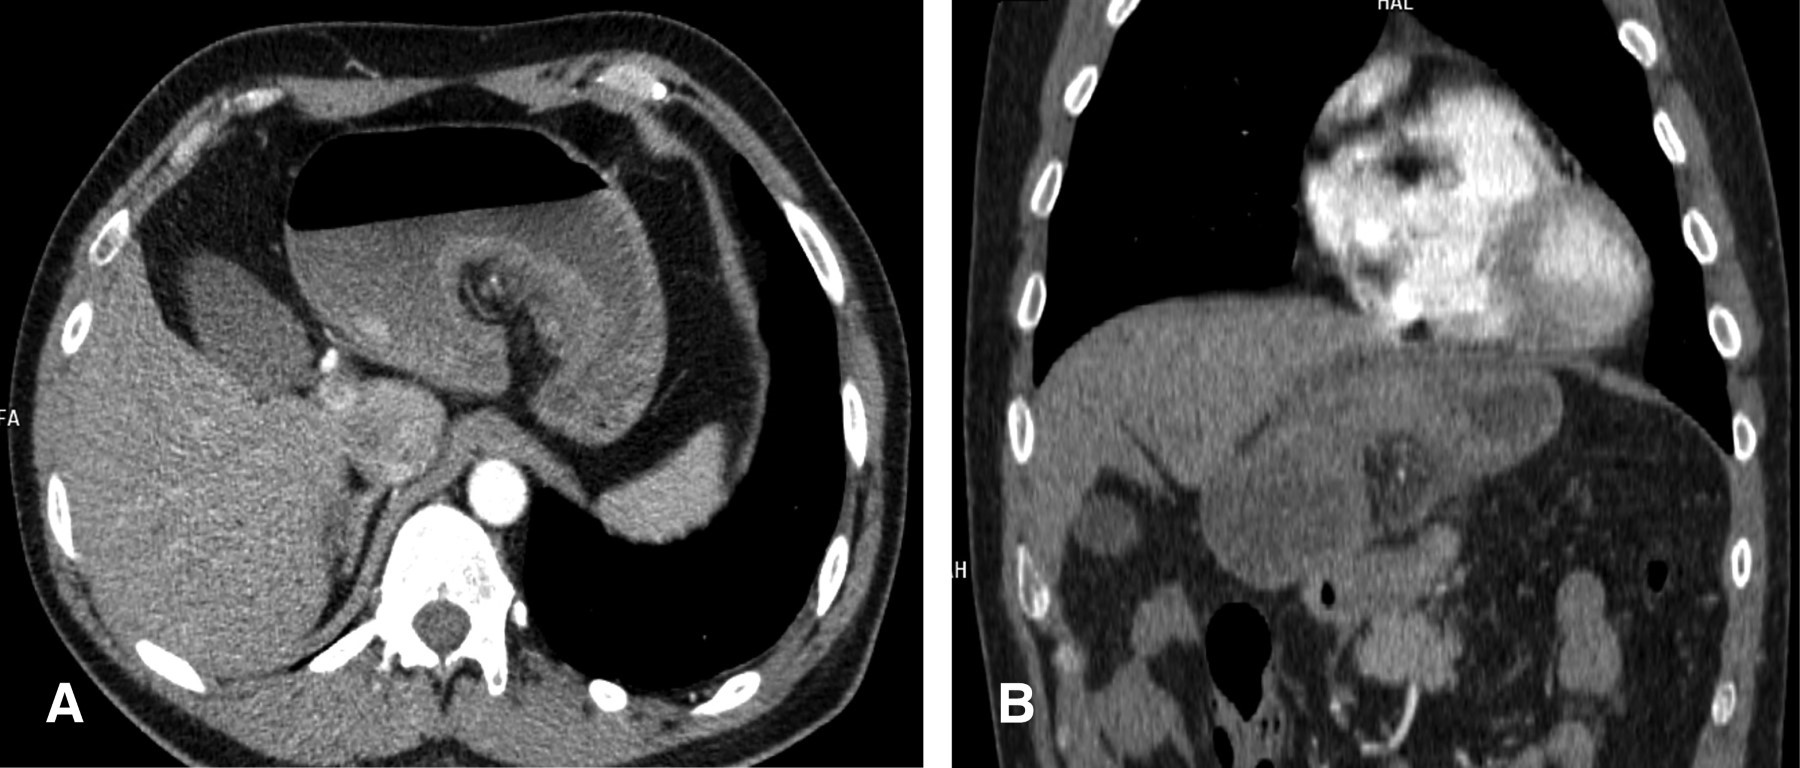

Hombre de 50 años de edad, quien como único antecedente relevante mencionó una funduplicatura laparoscópica 10 meses previos a su ingreso. Su padecimiento actual se caracterizó por la presencia de dolor abdominal de dos días de evolución, que progresó en intensidad hasta volverse incapacitante, refiriendo además irradiación al tórax posterior, náusea y arqueo sin vómito en múltiples ocasiones. Se realizaron estudios de laboratorio que evidenciaron: hemoglobina 17.1 g/dL, plaquetas 196,000/μL, leucocitos 9,300/μL, tiempo de protrombina 11 segundos, tiempo de tromboplastina parcial activada 27.5 segundos, glucosa sérica 101 mg/dL, BUN 16.1 mg/dL, creatinina sérica 1.1 mg/dL y lipasa sérica de 32 U/L. Se decidió llevar a cabo gastroduodenoscopía, donde se encontró dificultad para el paso del endoscopio al estómago y abundante contenido líquido (600 mm3), además de aspecto arremolinado y edematoso de los pliegues gástricos, lo que hizo sospechar un vólvulo gástrico (Figura 1).

El paciente fue hospitalizado y se le efectuó tomografía toracoabdominal, que reportó al estómago con engrosamiento de sus pliegues y signo de remolino hacia la región del píloro, confirmando la sospecha diagnóstica (Figura 2), por lo que se optó por la resolución quirúrgica urgente mediante laparoscopía, detorsión gástrica y gastropexia (Figuras 3 y 4). La evolución fue satisfactoria; un esofagograma con medio hidrosoluble de control posquirúrgico confirmó la ausencia de complicaciones a las 12 horas de la cirugía y el paciente pudo egresar para seguimiento por consulta externa tras cuatro días de estancia hospitalaria (Figura 5).

Figura 1

Figura 2